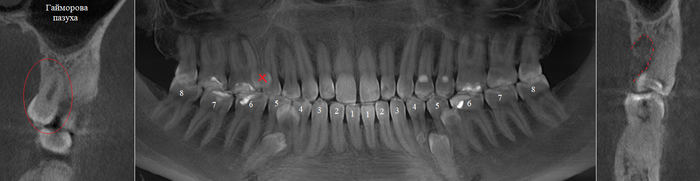

Согласитесь, не особо эстетично. Ортопантомограмма:

Фрагмент компьютерной томографии (вид сбоку):